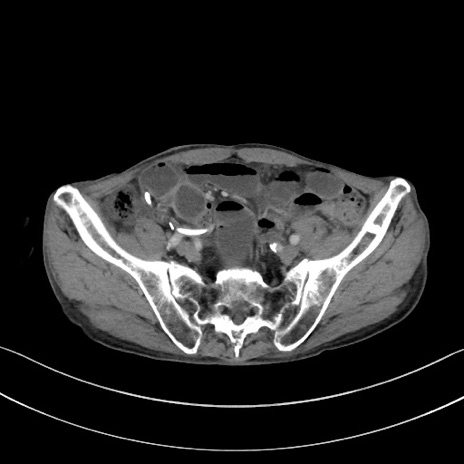

症例3(横断像)

【症例】 70歳代男性

【主訴】右鼠径部腫瘤、疼痛

【現病歴】本日朝より上記主訴あり、受診。

【既往歴】膀胱癌にて膀胱全摘、両側尿管皮膚瘻

【データ】WBC 5600、CRP 0.56